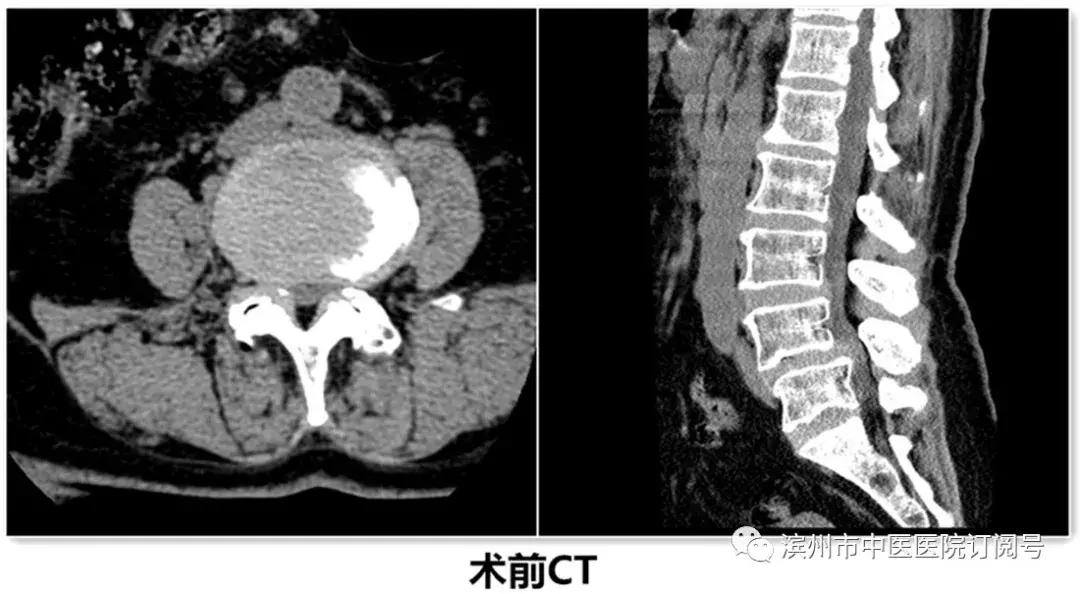

患者郭某,老年女性,因“反复腰部疼痛伴右下肢疼痛、麻木,不能行走”经多家医院诊治效果不好,遂来我院治疗。诊断为腰椎椎管狭窄并腰4/5椎体滑脱,入院后给予仔细查体及辅助检查。经检查该患者L4椎体退变性滑脱诊断较为明确,且伴有严重的椎管狭窄症状。由腰椎X线动力位片示腰椎不稳,腰椎融合术为最佳治疗方案。结合病人病情、年龄及身体条件,经腰椎间盘治疗中心团队反复论证,认为采取微创镜下融合术为最佳方案。刘维克主任介绍原本需要开放才能完成的手术现在微创下完成,需要攻克2个难点:一是需要在脊柱内镜下给予充分的减压,二是在微创通道下处理椎间盘和终板,并安全的植入融合器。

患者术后第3天带支具下床活动,症状基本消失,并行X线检查。见滑脱复位,且椎间隙高度恢复。